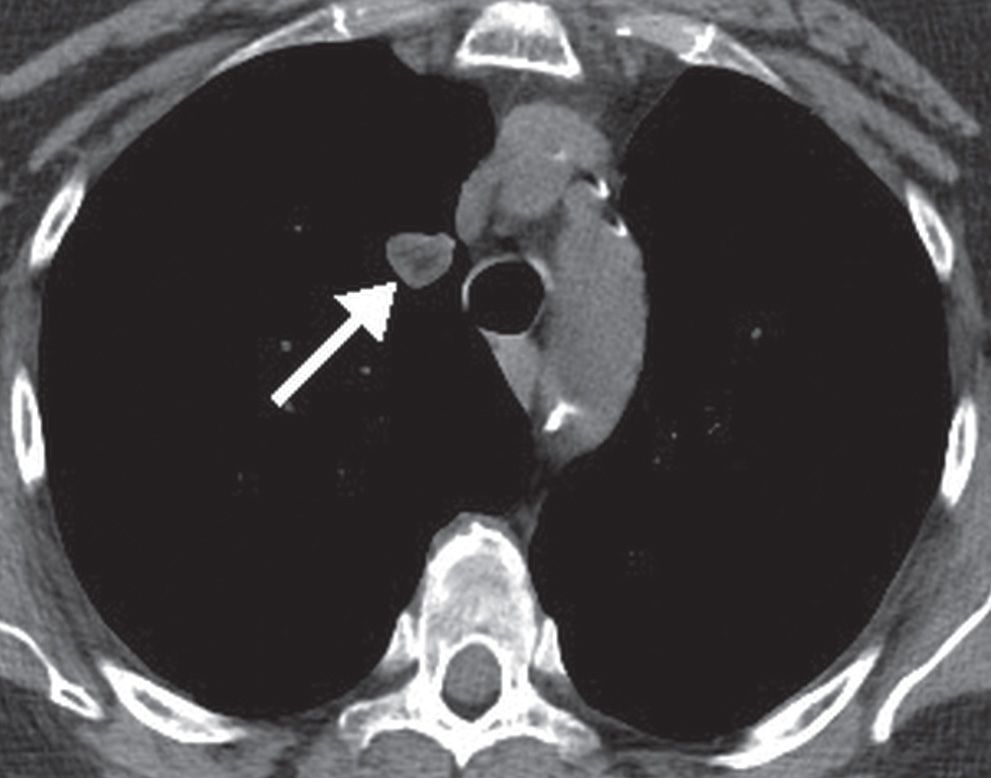

From radiologykey.com

Solitary and Multiple Pulmonary Nodules Radiology Key What Does Low Density Nodule Mean To determine whether the likelihood of lung cancer is high or low, physicians usually look at three distinct characteristics of the nodule: What does ‘lung nodule’ mean? Few nodules are found through manual palpation. Most lung nodules are not a sign of lung cancer and don’t require treatment. The size of the spot, its shape and. The phrase ‘lung nodule’. What Does Low Density Nodule Mean.